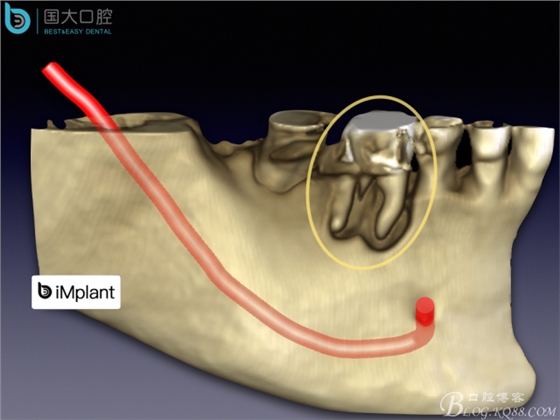

頰側骨壁嚴重缺失,應該如何設計種植位點?